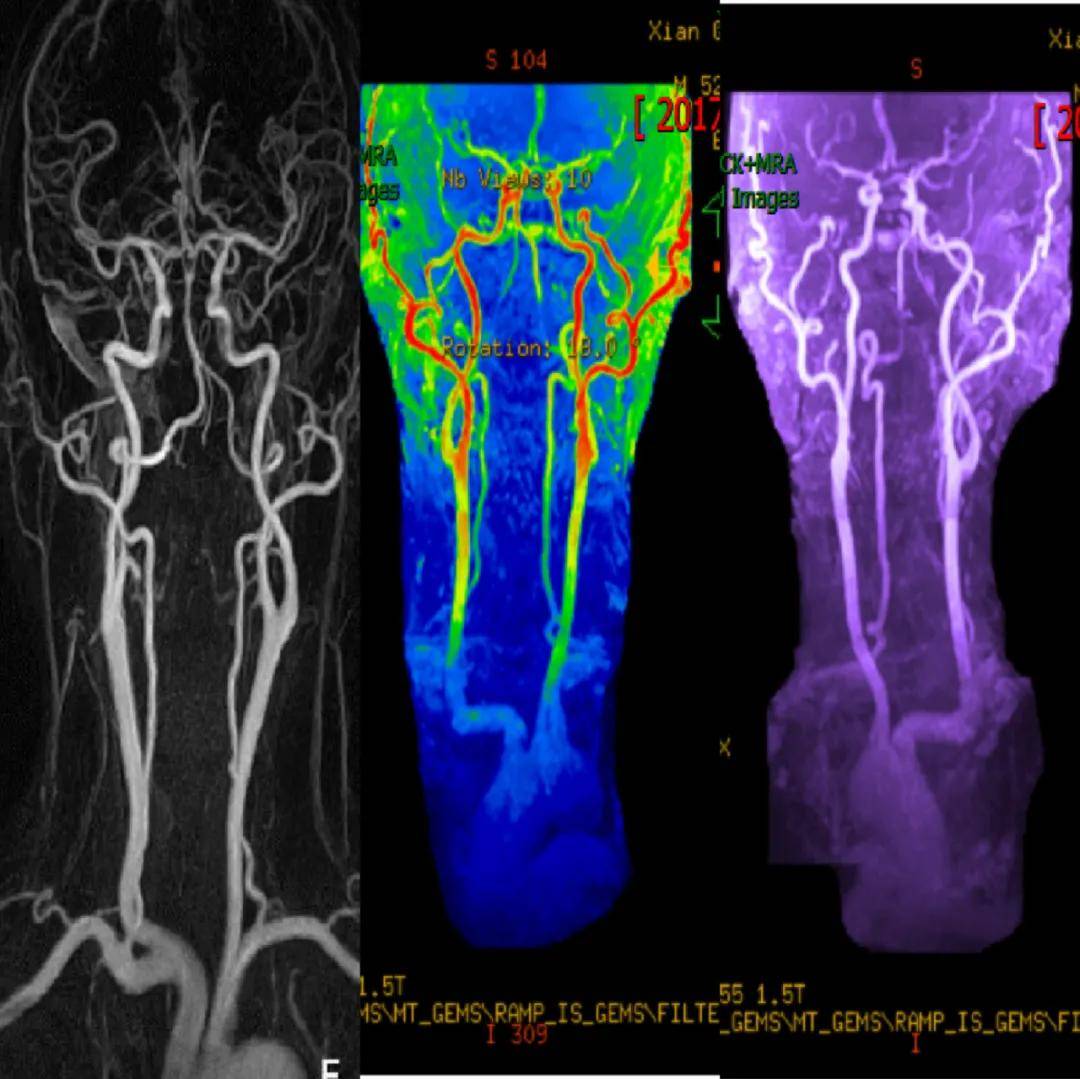

头颈部血管(MRA)